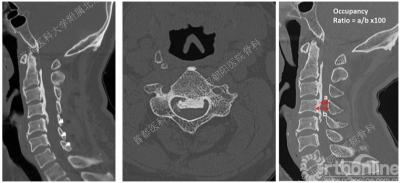

CT是诊断后纵韧带骨化的金标准,通过CT矢状位重建有助于辨别骨化块的大小和形状以及椎管狭窄的程度。

有研究表明,当骨化占有率(a/b x 100%)达到30%-60%时很可能发展为颈脊髓病。

在早期,Motoki等人根据椎管占有率和骨化后纵韧带形态选择手术入路,提出对于椎管占有率<60%及低平形态的骨化后纵韧带首选后路椎板切除术,而对于椎管占有率>60%及高隆形态、隆起成锐角的骨化后纵韧带首选前路手术。Takahito等人也提出,对于椎管占有率>60%的OPLL患者,尽管前路手术创伤较大,但术后症状改善和恢复率明显高于后路手术。

Takayuki等人提出可以通过K线(K-line)来选择颈椎OPLL手术方式。“K”代表后凸(Kyphosis),K线是指在颈椎X线侧位片上,通过C2和C7椎管中点的一条直线。根据骨化后纵韧带于K线的关系将其分为两类:K线(+)骨化后纵韧带未超过K线;K线(-)骨化后纵韧带超过K线。

K线定义